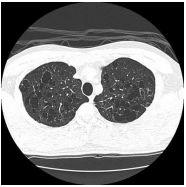

7.CC: cough for one year and back pain